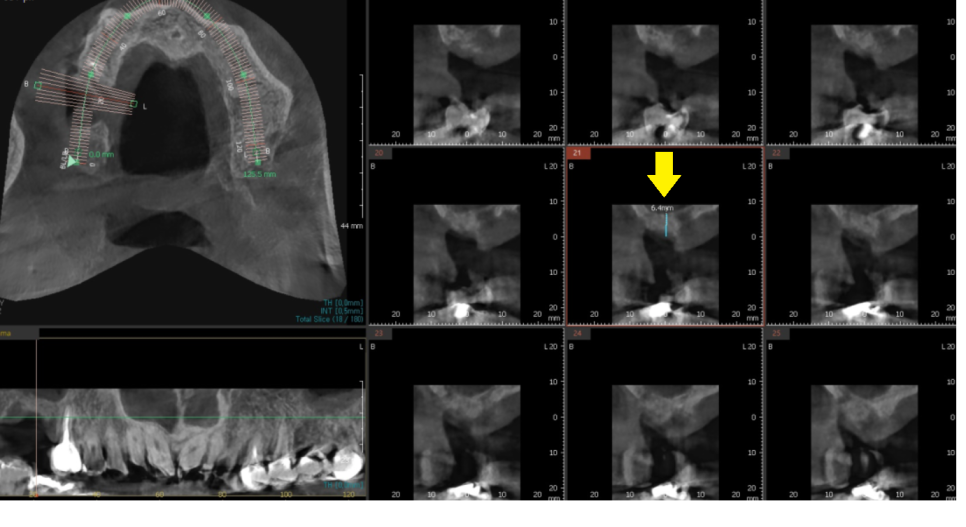

23.10.24

명일역 근처 치과에서 CT를 찍어보았을 때

하얀것이 뼈인데

치아 뿌리 부분으로 까만 것이 보이시죠?

주변 뼈가 다 녹을 정도로

고생하시다 오셨더라고요.